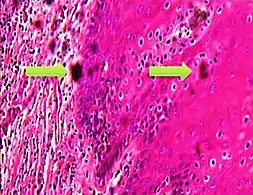

A crush artifact is an artificial elongation and distortion seen in histopathology and cytopathology studies, presumably because of iatrogenic compression of tissues. Distortion can be caused by the slightest compression of tissue and can provide difficulties in diagnosis.[2][3] It may cause chromatin to be squeezed out of nuclei.[4] Inflammatory and tumor cells are most susceptible to crush artifacts.[4]

4. 1 2 Chatterjee, Shailja (2014). "Artefacts in histopathology". Journal of Oral and Maxillofacial Pathology. 18 (4): S111–S116. doi:10.4103/0973-029X.141346. ISSN 0973-029X. PMC 4211218. PMID 25364159.

5. 1 2 3 Taqi, SyedAhmed; Sami, SyedAbdus; Sami, LateefBegum; Zaki, SyedAhmed (2018). "A review of artifacts in histopathology". Journal of Oral and Maxillofacial Pathology. 22 (2): 279. doi:10.4103/jomfp.JOMFP_125_15. ISSN 0973-029X. PMC 6097380. PMID 30158787.